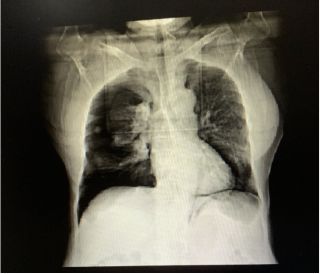

次日复查X光片,提示:

1、双侧气胸术后:右下胸腔肺野透亮度增高,待排少量气胸残留。

2、考虑双肺散在炎症。